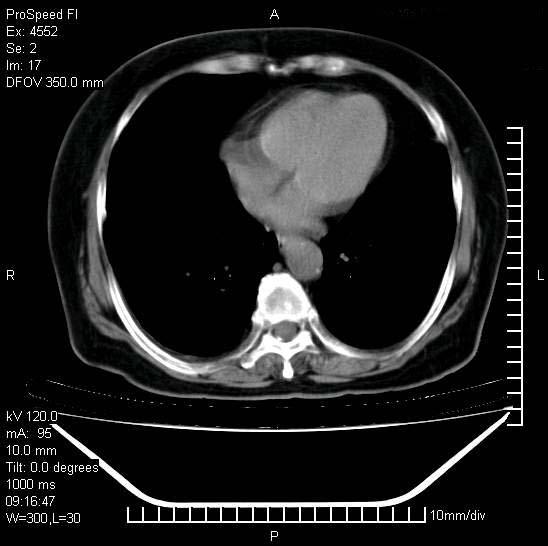

十几年前曾患肺结核,一周前突咳血约100ml,中性粒细胞稍高,诊断两上肺陈旧结核,下肺炎症,给予抗炎治疗,近几日晚上高热,39度,仍咳少量血,4天前ct及今天ct上传。

今天ct

短短几天内,病变范围明显增多扩大,以左侧明显,而且双侧出现胸水,还是考虑感染.

短短几天内,病变范围明显增多扩大,以左侧明显,而且双侧出现胸水,我更多考虑左侧中心性肺癌并并阻塞性不张及肺炎,炎症变化也太快了!

1)两肺结核并感染。2)不排除左肺上叶中央型肺癌并阻塞性肺炎、肺不张可能;建议行纤支镜检查。3)右肺门及纵隔淋巴结肿大。4)双侧胸腔积液。

陈旧性肺结核及左下肺不张,咯血后肺部感染,双胸腔积液,高热可能与痰液引流不畅有关。